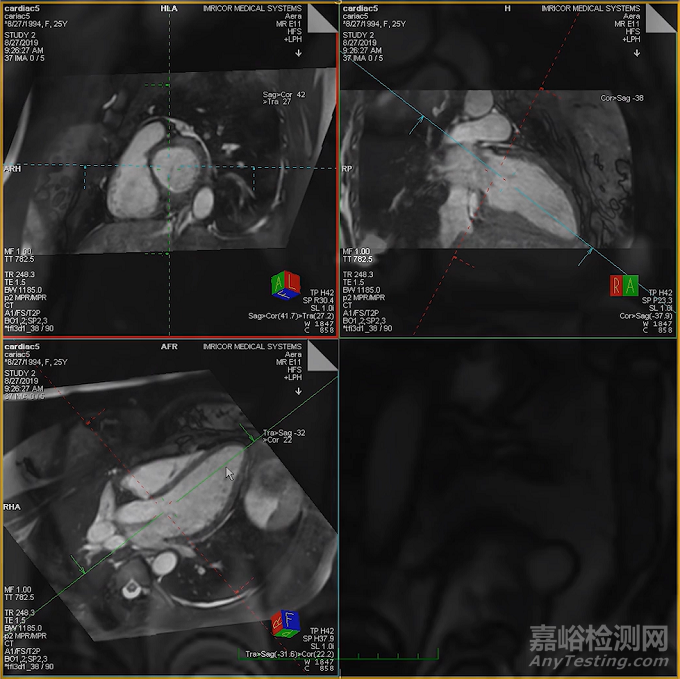

該產(chǎn)品是一款 9 Fr. 電生理診斷導(dǎo)管,設(shè)計(jì)用于實(shí)時(shí)磁共振成像(MRI)引導(dǎo)下的心臟電生理介入治療。這是 Imricor 首個(gè)獲得 FDA 批準(zhǔn)并進(jìn)入美國(guó)市場(chǎng)的醫(yī)療器械產(chǎn)品,也標(biāo)志著 MRI 引導(dǎo)電生理路徑在監(jiān)管層面邁出了關(guān)鍵一步。

此后,公司迅速發(fā)展成為全球首家也是目前唯一一家能為導(dǎo)管消融市場(chǎng)提供商業(yè)化可行且安全的iCMR產(chǎn)品的企業(yè),并于2019年8月在ASX上市,是創(chuàng)新的MRI兼容性醫(yī)療設(shè)備的領(lǐng)先開(kāi)發(fā)商,其開(kāi)發(fā)的設(shè)備可用于執(zhí)行MRI(磁共振成像)引導(dǎo)的心臟導(dǎo)管消融手術(shù)。

公司長(zhǎng)期專注于為心臟電生理與導(dǎo)管消融手術(shù)開(kāi)發(fā) MRI 兼容器械與系統(tǒng),其核心目標(biāo)是在 介入磁共振(interventional Cardiac MRI,iCMR) 環(huán)境下,完成完整的電生理標(biāo)測(cè)與消融流程。

在實(shí)時(shí) MRI 引導(dǎo)下,電生理醫(yī)生可以直接觀察心臟軟組織結(jié)構(gòu)、瘢痕分布及病變區(qū)域,為標(biāo)測(cè)與后續(xù)治療提供更直觀的信息基礎(chǔ)。

從技術(shù)本質(zhì)看,該路徑并非簡(jiǎn)單“更換影像工具”,而是試圖將 診斷、定位與結(jié)構(gòu)評(píng)估 更緊密地整合到同一影像體系中。